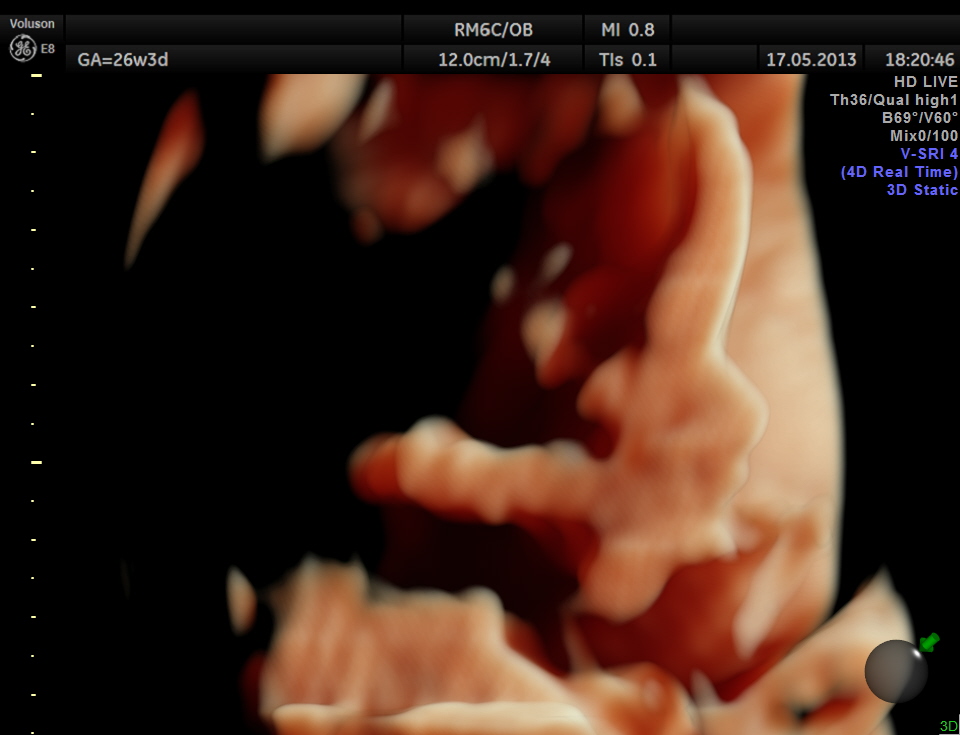

The limbs are shown below.

This fetus did not show any oro-facial clefts ; heart and spine appeared normal.